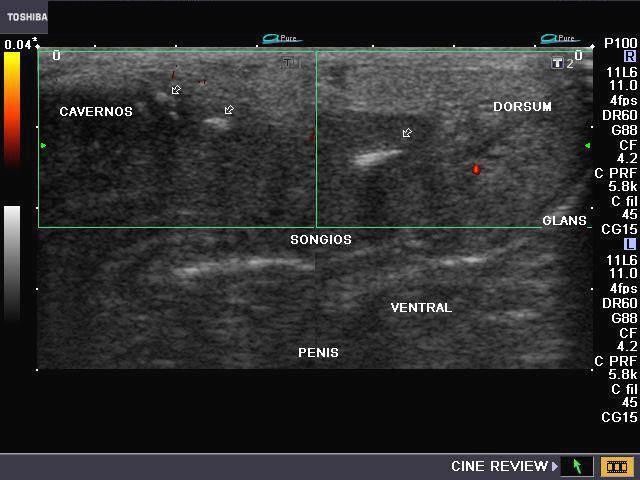

Penile AVM (arterio-venous malformation)/ AVM in the glans of penis

Ultrasound and Doppler images of vascular malformation of the glans penis

This male patient aged 50 yrs. presented with a bout of severe hemorrhage from the penile urethra during coitus for the past 2 days. Sonography and Color as well as Power Doppler imaging of the penis was done. Ultrasound/ Doppler flow images show marked vascularity along the glans of penis. Spectral Doppler waveforms show presence of both arterial and venous flow patterns in the vessels in and around the glans penis. These ultrasound, Power Doppler and Color Doppler images of the penis suggest arterio-venous malformation (AVM) in the glans penis. Trauma during coitus would have precipitated this episode of hemorrhage. The other differential diagnosis would be hemangioma of the glans penis.        (CORP SPONG= corpus spongiosum; CORP AV= corpus cavernosus; Dorsum= dorsal part of the penis). AVM and hemangioma of the glans penis are extremely and hardly any cases are reported in medical literature.